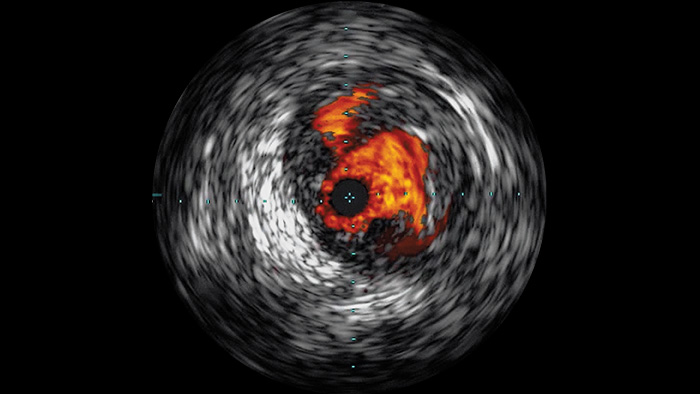

La ecografía intravascular (EIV) es una tecnología de imágenes basada en catéteres que permite a los médicos visualizar los vasos sanguíneos de adentro hacia afuera para ayudar a evaluar la presencia y el alcance de la enfermedad. La EIV ayuda a decidir, guiar y confirmar el tratamiento intervencionista adecuado para cada paciente.

Visualiza imágenes de alta definición de los vasos con un detalle vascular excepcional para apoyar las estrategias de tratamiento precisas, la navegación y el seguimiento.